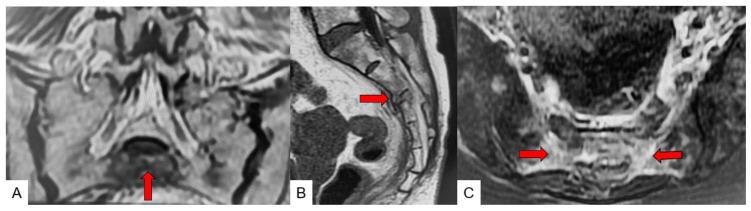

Sacral insufficiency fractures (SIF) are relatively rare fractures and difficult to diagnose on plain radiographs. The primary objective of the present study was to evaluate the role of lumbar magnetic resonance imaging (MRI) for the diagnosis of SIF. The secondary objective was to identify the classification of SIF by computed tomography (CT).

The sensitivities for SIF were 28.5% in radiographs and 94.2% in CT, and all fractures were detected in MRI. MRI showed a more complex fracture pattern compared with CT in 65% of the cases. We observed 71.4% of single SIFs, 9.1% with other spinal fractures, 13.0% with other pelvic fractures, and 7.8% with other fractures. According to the SIF fracture pattern, the H/U type was 40.2%, transverse type was 33.7%, λ/T type was 24.7%, unilateral vertical type was 1.3%, and bilateral vertical type was 0%.

CONCLUSIONS

an MRI of the lumbar spine including the sacrum with a coronal fat-suppressed T2-weighted image is useful for elderly patients with suddenly increasing low back pain at an early stage. This procedure improves an early SIF detection, recognition of concomitant pathologies, and adequate treatment for the patients.

骶骨不全骨折(SIF)是相对罕见的骨折,在普通X线片上难以诊断。本研究的主要目的是评估腰椎磁共振成像(MRI)在SIF诊断中的作用。次要目的是通过计算机断层扫描(CT)确定SIF的分类。

X线片对SIF的敏感性为28.5%,CT为94.2%,MRI能检测到所有骨折。65%的病例中,MRI显示的骨折类型比CT更复杂。我们观察到71.4%为单一SIF,9.1%合并其他脊柱骨折,13.0%合并其他骨盆骨折,7.8%合并其他骨折。根据SIF骨折类型,H/U型占40.2%,横型占33.7%,λ/T型占24.7%,单侧垂直型占1.3%,双侧垂直型占0%。

结论

对伴有骶骨的腰椎进行MRI检查,包括冠状位脂肪抑制T2加权成像,对早期突然出现下腰痛的老年患者有用。该检查可提高SIF的早期检测率,识别合并病变,并为患者提供适当治疗。